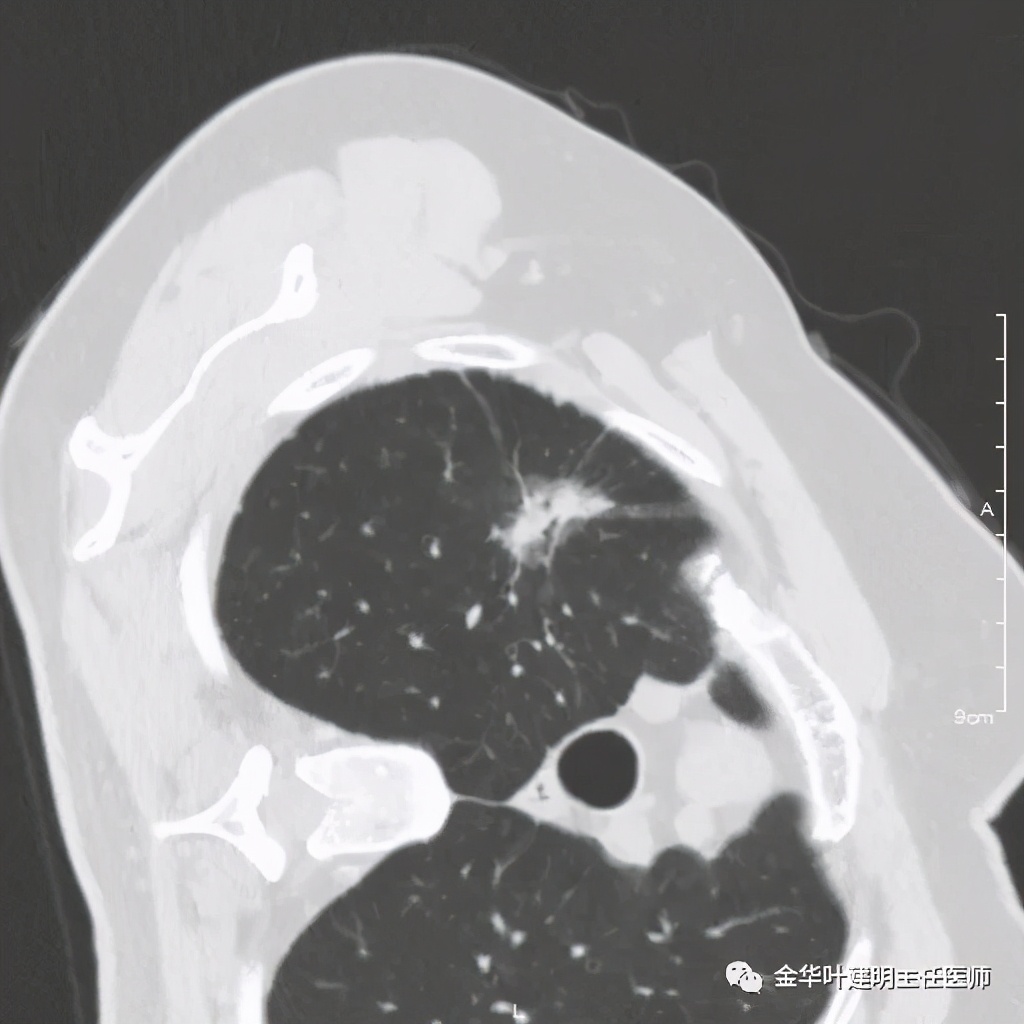

五、浸润性腺癌之粘液腺癌:

影像特征:这个病例是我在术前仅凭影像就判断其为粘液腺癌,术后确诊的。粘液腺癌表现为 实性乏收缩力、密度较均匀 的实性结节。病灶的边界一般非常清楚,没有毛刺、磨玻璃、卫星灶等,但又乏收缩力,像本例紧贴胸膜也不会有牵拉凹陷;同时病灶的密度又比较均匀(粘液成份)。良性肿瘤密度要更高些、慢性炎没有这么光整的边界,也容易有瘢痕收缩方面的影像表现、其他实性的腺癌则要有收缩力、腺泡型虽然也缺乏收缩力,但密度要不均匀些。